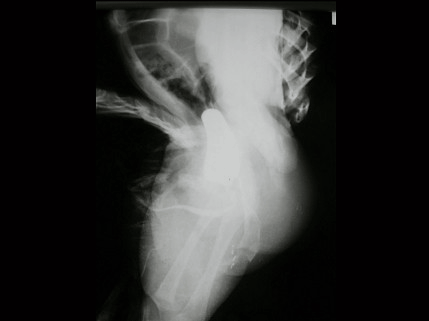

5.

男,4个月,阴茎、排尿异常4个月,行尿道造影如图所示,最可能的诊断是 ( )

A.

正常尿道

B.

尿道瓣膜形成

C.

尿道下裂畸形

D.

尿道憩室

E.

尿道重复畸形